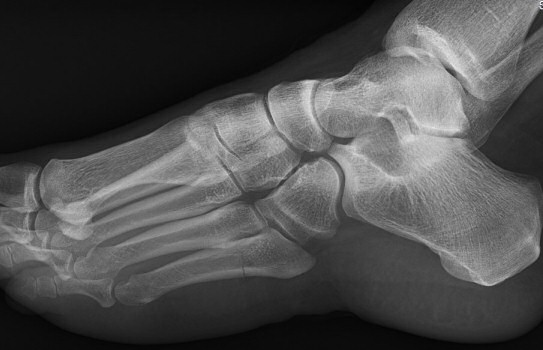

Mellan de röda strecken: ungefärligt läge för Jones-fraktur. Längre proximalt: avulsionsfraktur.

Exempel på Jones-frakturer, första bilden färsk, andra bilden ej läkt, tredje bilden efter operation.